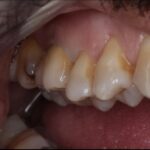

E-Max

L’E.max®, 100% céramique, est à base de disilicate de lithium, reconnu pour sa haute résistance à la flexion (500 Mpa).

Elle est donc une alternative esthétique aux restaurations céramo-métalliques, conservant, ensemble, éclat et durabilité.

Couronne, bridge de 3 éléments, inlay, onlay, facette